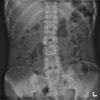

- X-ray

① 추체의 음영 감소, 척추 주위 연부조직의 음영 증가

② 골단판의 불규칙성, 추간판 간격의 협소

③ 후기 후만증, 측만증 등의 척추 기형

X-ray : 척추 결핵(Spinal tuberculosis)